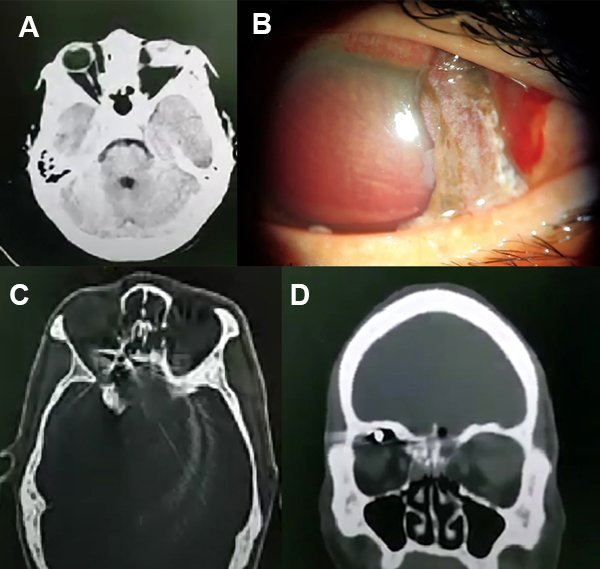

Hombre de 31 años consultó por traumatismo en OI en contexto de riña con arma de fuego de 7 días de evolución. Al examen oftalmológico se constató AV en OD de 7/10 sin corrección y amaurosis en OI. Al examen externo el OD se presentaba con una ptosis leve y el OI en hipotropía con limitación a la supraducción. A la biomicroscopía, el OD tenía un hematoma bipalpebral con hemorragia subconjuntival de 360° en reabsorción. En el OI se observaba una alteración anatómica del segmento anterior con atalamia e hipema total y una herida escleral en hora 1 que se extendía hacia posterior con protrusión de contenido intraocular por la misma (fig. 4A). La PIO de OD era de 14 mmHg y en OI se constató hipotonía digital. En el fondo de ojo del OD se observó vítreo claro, retina aplicada, papila con bordes netos con excavación de 0,1. El fondo de ojo del OI no se podría observar mediante OBI por opacidad de medios. Se solicitó TC de órbita (fig. 4B-C-D) que mostraba múltiples imágenes hiperdensas en cavidad orbitaria derecha con aparente globo ocular deforme y desorganización de estructuras de globo ocular izquierdo. Se consultó con los servicios de neurocirugía y otorrinolaringología del hospital y refirieron que no había necesidad de intervención quirúrgica de manera inmediata. Se internó con antibióticos endovenosos, exploración y reparación quirúrgica OI con postoperatorio favorable. Con respecto del OD, se decidió conducta quirúrgica expectante y tratamiento médico tópico.

Figura 4. A) Herida perforante esclerocorneal con salida de contenido por ella misma en ojo izquierdo. B y C) TC donde se observa desorganización de estructuras del ojo izquierdo y múltiples imágenes hiperdensas en órbita derecha (metal). D) Tomografía computada, corte coronal, con imagen hiperdensa superior a globo ocular derecho (círculo amarillo).